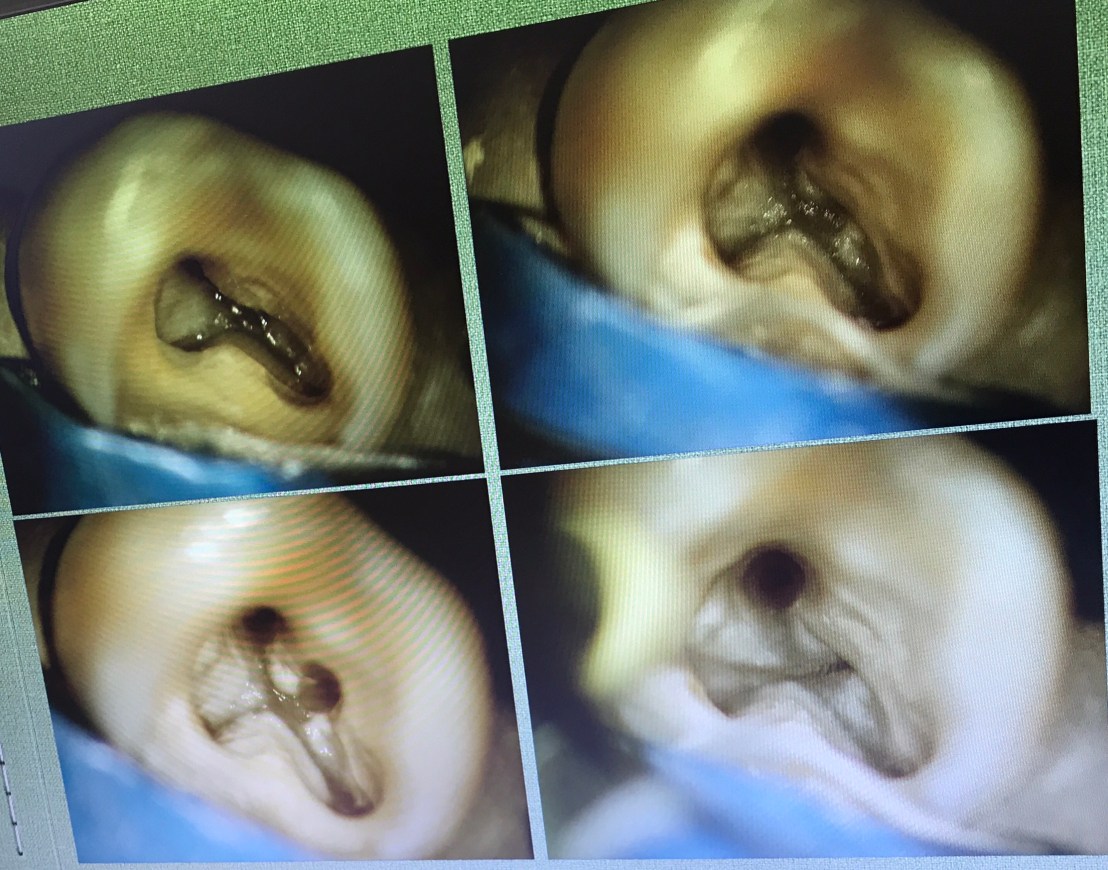

งานที่ใช้เยอะมาก การ Locate canal หา MB2

อย่างที่บอก ท่านอาจารย์แนะนำว่า ควรมี Mind set ไว้ในใจว่า ฟัน molar บน จะมี MB2 อยู่ในตำแหน่งที่ค่อนมาทาง Palatal ต่อ MB1 เล็กน้อย

ฟันที่มี MB2 อยู่ที่ 95.2% (ซึ่งจะเห็นว่าเยอะมาก)

ถ้าเราใช้ตาเปล่าหา MB2 จะมีโอกาสเจอที่ 17.2%

แต่ถ้าใช้ MC จะมีโอกาสหาเจอเพิ่มขึ้นเป็น 71.1%

ตำแหน่ง MB2 จะห่างจาก MB1 ไม่มาก

อันนี้ใช้วิธีดูจากฟองอากาศขณะ IR ที่เกิดบริเวณ orifice ครับ

ทิศทางการกรอ จะไม่ remove ส่วน floor ครับ แต่กำจัดเฉพาะส่วนที่ Calcified

ลองสังเกตเส้นที่ลาก ตำแหน่งของ MB2 จะอยู่ mesial ต่อเส้นนี้ที่ระยะประมาณ 1-2.5 มม.

แนวเส้นประสีแดง คือ บริเวณที่จะพบ MB2